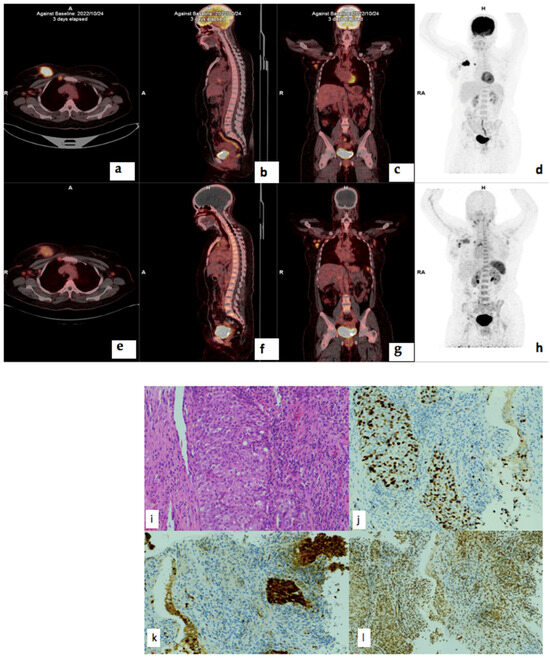

3.5. Treatment Response

3.7. Correlation of PET/CT Metrics with CXCR4 Immunohistochemistry Staining